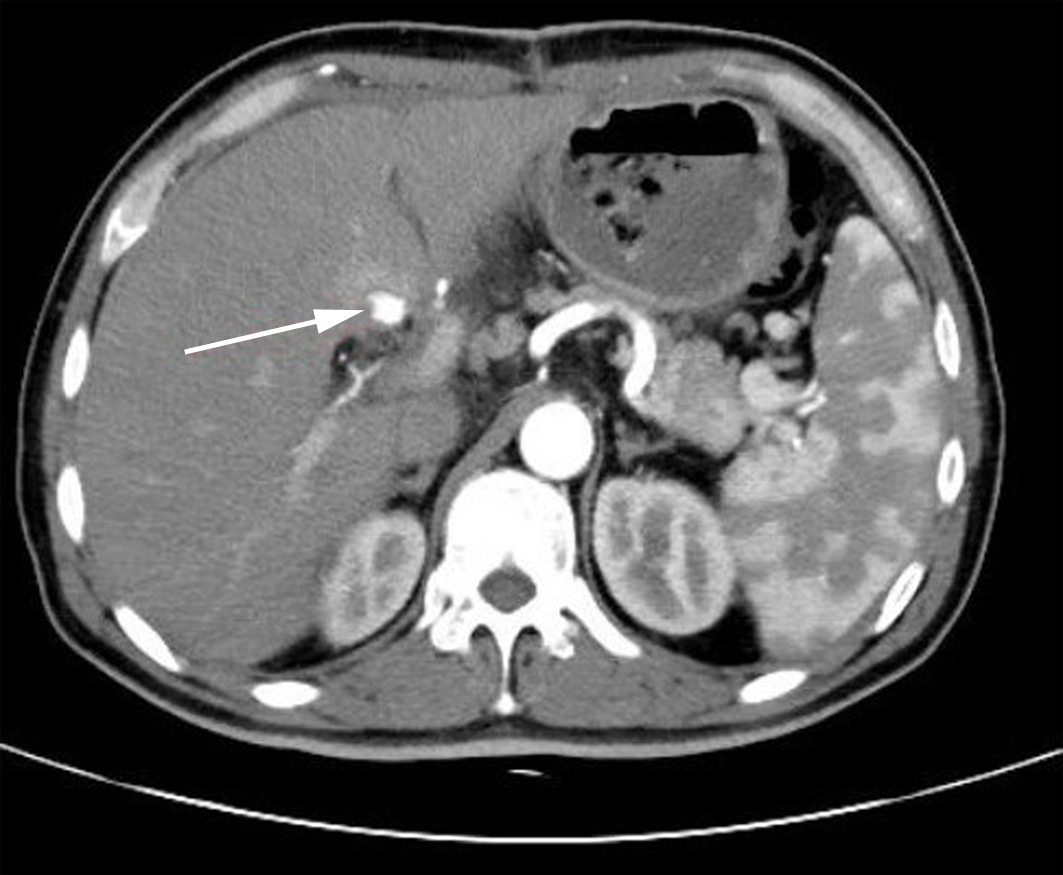

Value of 18F-FDG PET/CT, contrast-enhanced ultrasound, and their combined use in differential diagnosis of benign and malignant pancreatic lesions: A comparative study

Lichun ZHENG, Xiaoming ZHANG, Tianying YU, Jie LI, Xiaoqian DENG, Xiangliu OUYANG

2022, 38(12): 2774-2779. DOI: 10.3969/j.issn.1001-5256.2022.12.017

Abstract(2246) HTML (1599) PDF (3391KB)(53)

Abstract:

Objective  To assess the value of 18F-FDG PET/CT, contrast-enhanced ultrasound, and their combination in the differential diagnosis of benign and malignant pancreatic lesions.  Methods  A retrospective analysis was performed on patients with pancreatic lesions who underwent18F-FDG PET/CT and contrast-enhanced ultrasound who were admitted to Tangshan Gongren Hospital from January 2015 to December 2020. The imaging results were confirmed by pathology examination to evaluate diagnostic sensitivity, specificity, accuracy, positive and negative predictive value. The t-test was used for comparison of continuous data between two groups, and the chi-square test was used for comparison of categorical data between groups.  Results  There were 83 malignant lesions and 25 benign lesions in 108 patients. The sensitivity, specificity, accuracy, positive and negative predictive value were 86.75%, 80.00%, 85.19%, 93.51% and 64.52% for 18F-FDG PET/CT; and 69.88%, 76.00%, 71.30%, 90.63% and 43.18% for contrast-enhanced ultrasound, respectively. The two methods differed significantly in sensitivity and accuracy (all P < 0.05), but not in specificity, negative and positive predictive value (all P > 0.05). When combined with the contrast-enhanced ultrasound, 18F-FDG PET/CT had an increased sensitivity, specificity, accuracy, positive and negative predictive value of 90.36%, 84.00%, 88.89%, 94.94% and 72.41%, respectively, though this was not statistically significant due to the increased signal of blood supply in the lesions.  Conclusion  18F-FDG PET/CT has a better performance than contrast-enhanced ultrasound in the differential diagnosis of benign and malignant pancreatic lesions, and their combination can improve the diagnostic value.